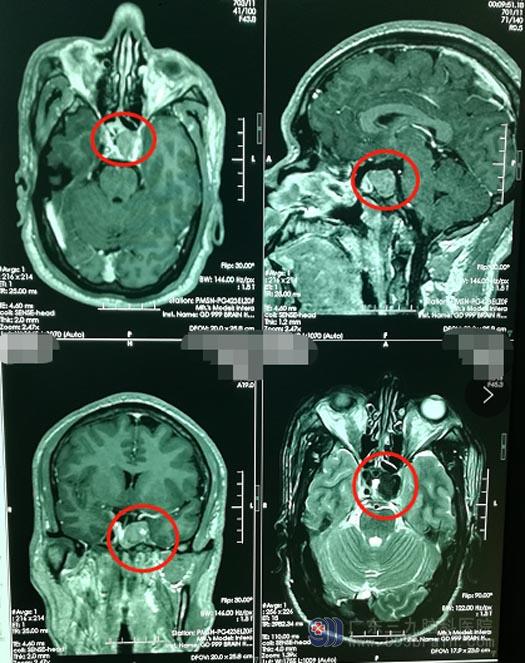

今年,裴先生在单位组织的常规体检中,发现血压偏高,体检医生建议他做个头颅MR检查,结果显示“鞍区占位性病变,考虑垂体瘤”。

裴先生和家人商量后,一致同意手术治疗。鲁明带领神经外五科手术团队为裴先生实施了“内镜下经鼻蝶侵袭性垂体瘤占位切除术”,术中将肿瘤全切。术后未出现脑脊液漏;病理检查结果:(鞍区)密颗粒型生长激素细胞腺瘤。现在,裴先生已顺利康复出院。